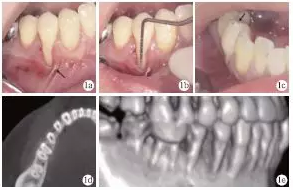

臨床檢查發(fā)現(xiàn),患者全口牙齦無(wú)明顯紅腫,探診深度1~4mm,BOP(+)<15%;#44頰側(cè)牙頸部充填物,頰側(cè)可見(jiàn)9mm齦退縮,超過(guò)膜齦聯(lián)合,僅存小于1mm的角化齦,且近中見(jiàn)系帶附著,近遠(yuǎn)中齦乳頭均存在輕度退縮(圖1a、1b);正中咬合時(shí)可捫及#44功能性動(dòng)度,頰尖舌斜面可見(jiàn)咬合高點(diǎn)(圖1c)。術(shù)前CT見(jiàn)#44頰側(cè)牙槽骨吸收達(dá)根尖1/3,鄰面擴(kuò)展達(dá)根間區(qū),鄰面牙槽骨高度降低(圖1d、1e)。根據(jù)臨床檢查和CT檢查,診斷為#44Miller Ⅲ°牙齦退縮。

圖1 術(shù)前臨床及X線(xiàn)檢查